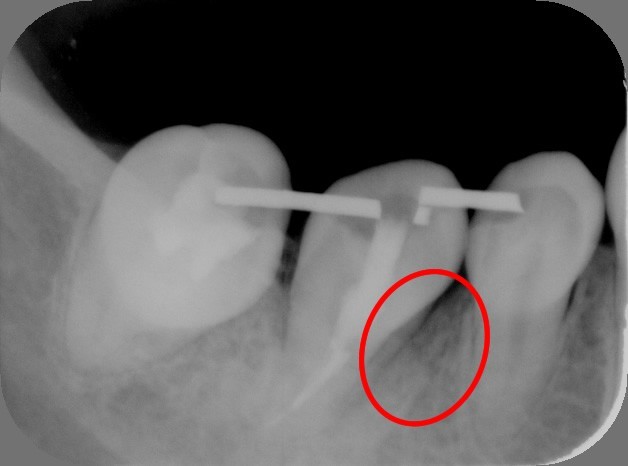

3.上の親知らずを下へ移植直後